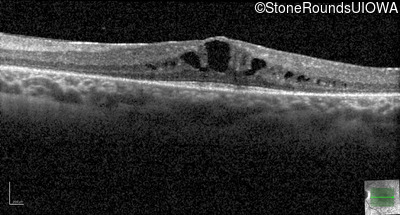

Optical Coherence Tomography - Right - 20/25 -2

Exemplar / OCT Stack